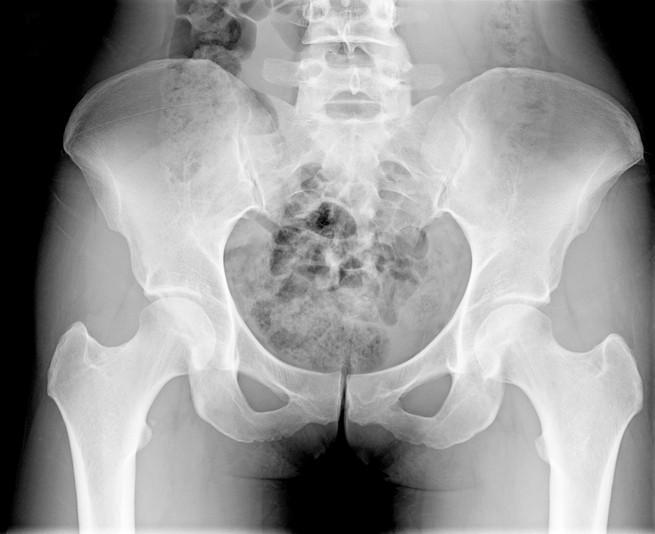

Shelby’nin üç çocuğu daha vardı ve hamileliği sırasında kendisine bebeklerinin iri olacağı yönünde uyarılar yapılmıştı. Ancak, 60 kilogramlık bir bebek doğuracağını hiç tahmin etmiyordu. “Bebeğimin 5 kilo 900 gram olacağını asla aklıma getiremezdim, ama şu anda karnımın fotoğraflarına bakıp, ‘Olmalıydı’ diyorum” şeklinde konuştu. Hamilelik sürecinde sık sık ‘Sağ çıkamayabilirim’ diye endişelendiğini ifade eden Shelby, fizik tedavi uzmanı tarafından da, bebeğin kalça kemiğini zarar verdiğinin söylendiğini açıkladı.

Doktorlar, Ali Atilla’nın 37 haftalık iken dünya geldiğine ve literatürde yer alabilecek büyüklükte olduğunu bildirdi. Kadın Doğum Uzmanı Dr. İbrahim Yaşa, “Bebeğin 6 kiloya ulaşması, Türkiye’de en büyük bebekler arasında yer almasını sağladı. Geçen yıl İspanya’da ise 6 kiloluk bebek gündeme gelmişti. Bizim bebeğimiz, özellikle bu standartlar içinde oldukça büyük” açıklamasında bulundu.